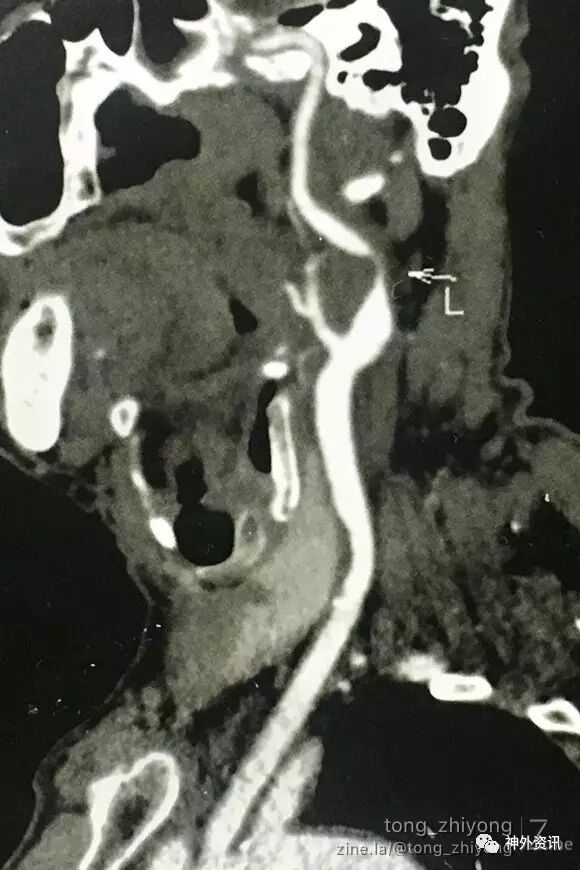

老年,男性,症状性左侧颈动脉重度狭窄

左侧颈内动脉高位狭窄:狭窄位于C2椎体水平,下颌角后上方

狭窄部位局限,颈内动脉稍迂曲

术中血管造影显示:颈动脉通畅,管径增宽,迂曲解除